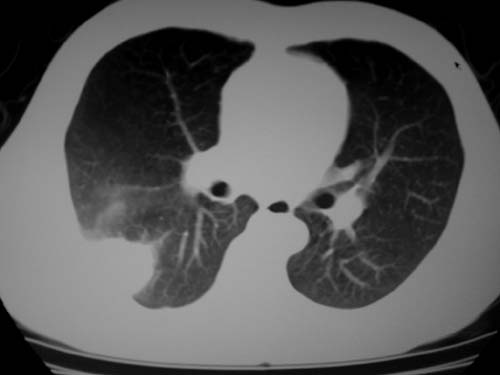

标题: CT19540: 31岁。自述结核性胸水治疗两个月后,在外院拍x线发 [打印本页]

标题: CT19540: 31岁。自述结核性胸水治疗两个月后,在外院拍x线发

右侧胸壁结节状软组织影伴相应肺叶内受侵,伴右侧胸腔积液。考虑:结核性可能大。

支持 右侧胸壁结节状软组织影伴相应肺叶内受侵,伴右侧胸腔积液。考虑:结核性可能大。

右侧胸壁结节状软组织影伴相应肺叶内受侵,伴右侧胸腔积液,结合临床,首先考虑结核。

考虑结核性胸膜炎,胸膜肥厚,不除外胸膜间皮瘤可能,建议复查。

1)考虑右侧结核性胸膜结节。2)右侧胸膜增厚+包裹性胸腔积液。